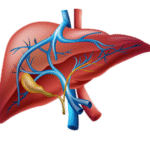

Liver Function Test (LFT) – Comprehensive Panel

A complete assessment of liver health, used to detect liver inflammation, infection, or damage due to alcohol, hepatitis, or medications.

- Liver